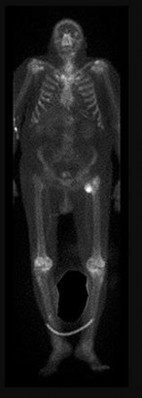

Question 2:

A 12-year-old boy presents with left thigh pain, an antalgic gait, and an externally rotated left lower extremity. Radiographs demonstrate the pathology shown. Which of the following is considered an absolute indication for prophylactic pinning of the asymptomatic, contralateral hip in a patient presenting with Slipped Capital Femoral Epiphysis (SCFE)?

Correct Answer: Underlying endocrine disorder (e.g., hypothyroidism)

Explanation:

SCFE is characterized by a displacement of the proximal femoral epiphysis. Prophylactic pinning of the contralateral hip is somewhat controversial but generally recommended in patients with a high risk of subsequent contralateral slip. Absolute indications or highly strong recommendations for prophylactic contralateral pinning include an underlying endocrine disorder (such as hypothyroidism or growth hormone deficiency), renal osteodystrophy, previous radiation therapy, and presentation at a very young age (e.g., < 10 years). Endocrine disorders dramatically increase the risk of bilateral involvement, often occurring simultaneously or sequentially.